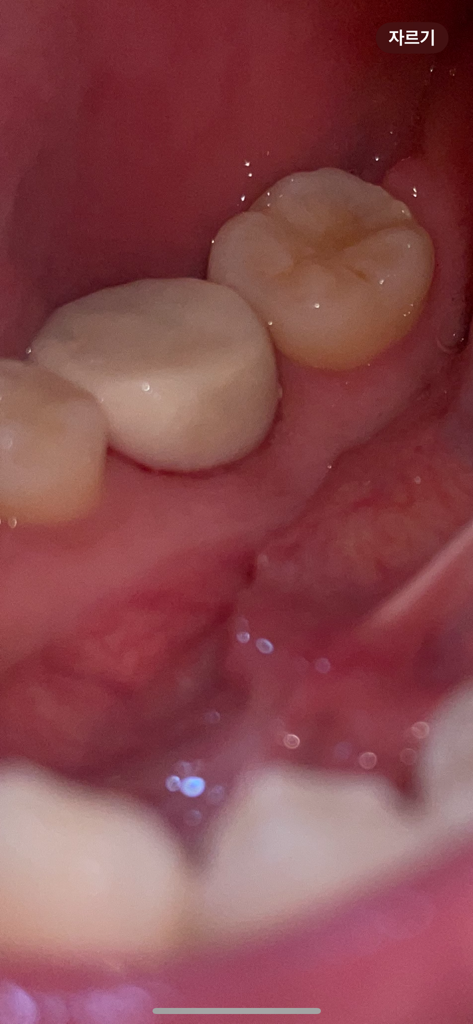

혀 로도 틈이 느껴져요

이러면 음식물이 끼거나 하지않나요??

다시 임시치아를 해야하는지 궁금합니다

또한 음식물이 끼게 되면 충치가 생길 수도있나요?

임시치아는 말그대로 임시로 사용하는겁니다. 저정도면 크게 문제가 생기는건 아니니 너무 걱정하지마세요.

해당 틈에 음식물 찌꺼기가 낄수 있기에 양치시에 치실 및 치간칫솔을 이용하여 사이틈의 이물질을 꼼꼼히 제거하길 권합니다.

임시치아라 틈이 있을 수도 있습니다. 양치질 최대한 꼼꼼히 해주시면 되고 다시 할 필요는 없어보입니다.

이정도 틈은 임시치아임을 고려하면 그리 큰 건 아닙니다만 관리를 잘해주시긴 해야 합니다. 워터픽 등을 이용하여 음식물이나 치태가 끼지 않도록 잘 관리해주시기 바랍니다.

크라운 치료를 할 때 하는 임시 치아이는 틈이 생길 수 있습니다. 보철을 제작을 하게 되면 해당 부위에 틈이 없어지기 때문에 큰 문제가 되지는 않기 때문에 해당 부위를 자극하지 않는 것이 좋습니다. 불편감이 있다면 치과에서 임시 치아를 수정해줄 수 있습니다